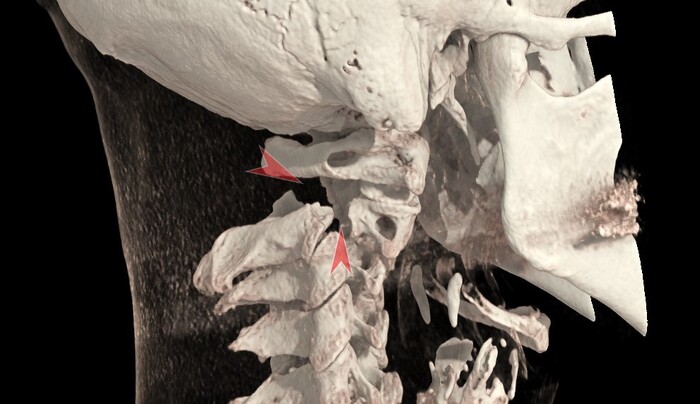

И на 3Д-реконструкции:

Данный тип перелома имеет своё название: перелом висельника (или перелом палача, или перелом Хангмана). Впервые был описан у повешенных в 1913 году. В 1964 году R. C. Schneider и соавт. опубликовали статью, в которой указывалось на сходство повреждений шейного отдела позвоночника при дорожно-транспортных происшествиях и у повешенных. Термин "перелом Хангмана" возник как сленговое произношение "hangee" fracture -> "hangman fracture".

Механизм перелома экстензионно-дистракционный (экстензия - разгибание, дистракция - растяжение). Перелом сопровождается повреждением связочного аппарата позвоночника (в частности передней и задней продольной связки), что дополнительно усиливает его нестабильность.